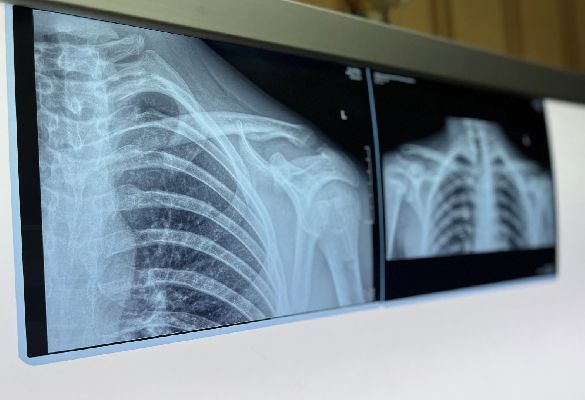

Как отметил заведующий отделением лучевой диагностики МОДКТОБ Антон Фомченко, каждый метод имеет свои особенности. По его словам, рентгенография, как правило, применяется в первую очередь при подозрении на переломы и другие повреждения костей.

Компьютерная томография обеспечивает более детализированные послойные изображения и используется для оценки сложных травм, включая поражения костных структур и отдельных мягких тканей. Магнитно-резонансная томография, в свою очередь, наиболее информативна при исследовании мягких тканей — связок, мышц, хрящей и позвоночника.

Специалист подчеркнул, что в ряде случаев для уточнения диагноза может потребоваться проведение нескольких исследований. Такой подход позволяет получить более полную картину состояния пациента и выбрать наиболее эффективную тактику лечения.